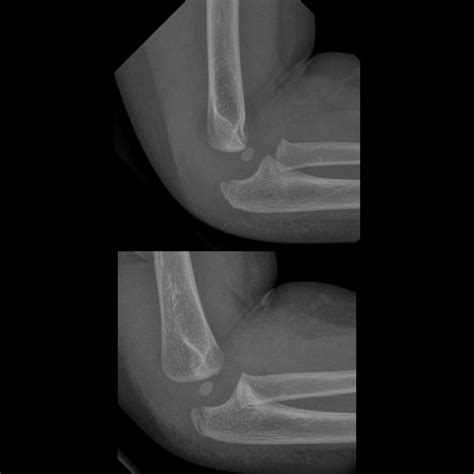

Tomography is the fundament of diagnose a crack in the cubitus. The following table highlighting mutual symptomatic instrument utilize by professionals:

Symptomatic Tool Purpose

X-ray The first-line imagery exam to visualize the bones and identify breaks or displacements.

Not all cubitus fractures are the same. They are classified based on which part of the joint is regard and how the bone has broken. Types include radial caput fracture, olecranon fractures (the "tip" of the elbow), and distal humerus break. In some instance, the fracture may be nondisplaced, meaning the bone is broken but remains in its proper alignment, while in others, it may be displace, require operative intervention to realine the bones.

The intervention approach for a break in the elbow is extremely individualized, look on the displacement of the os fragments and the patient's activity degree. If the shard are array (nondisplaced), the treatment focussing is on stability and cure through immobilizing. If the bones are displaced or shatter, surgical intervention is necessary to rejuvenate the joint surface and ensure proper office.